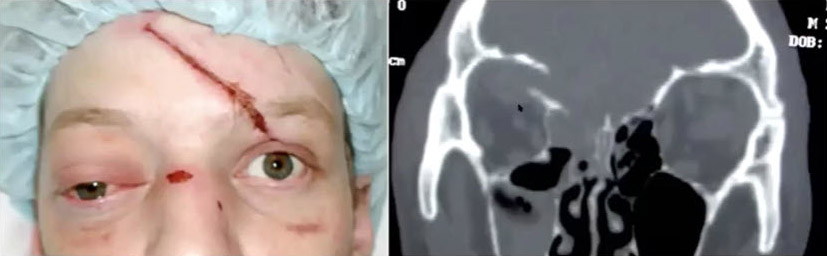

Now, let's look at orbital floor fractures. These fractures tend to occur in slightly older children when the maxillary sinus develops, and it’s where we see the most serious problem in the eye. The Trapdoor fracture—or white-eye blowout as we call it—is a pediatric problem, and it’s extremely rare in adults. The patient will often present with no bruising or swelling. They look fine except they may have nausea and vomiting. However, they will have pain if they move their eye, and sometimes they don’t want to open their eyes because it hurts, so they’re squinting. This unique pediatric injury involves the squeezing of the inferior rectus muscle in the fracture site. That muscle, if not released, will undergo necrosis and the patient will have diplopia for the rest of their life, so this is an emergency. They might present squinting, or they cannot look up when asked—which is a big concern. The key is to take them emergently to the operating room in order to release the trapdoor, enlarge the fracture and free up the inferior rectus muscle.

Roof fractures can be significant issues, so when you're in the emergency room you want to check if the patient has double vision, if they can move their eye, if they have ptosis, if they have mydriasis. These are important things to rule out.